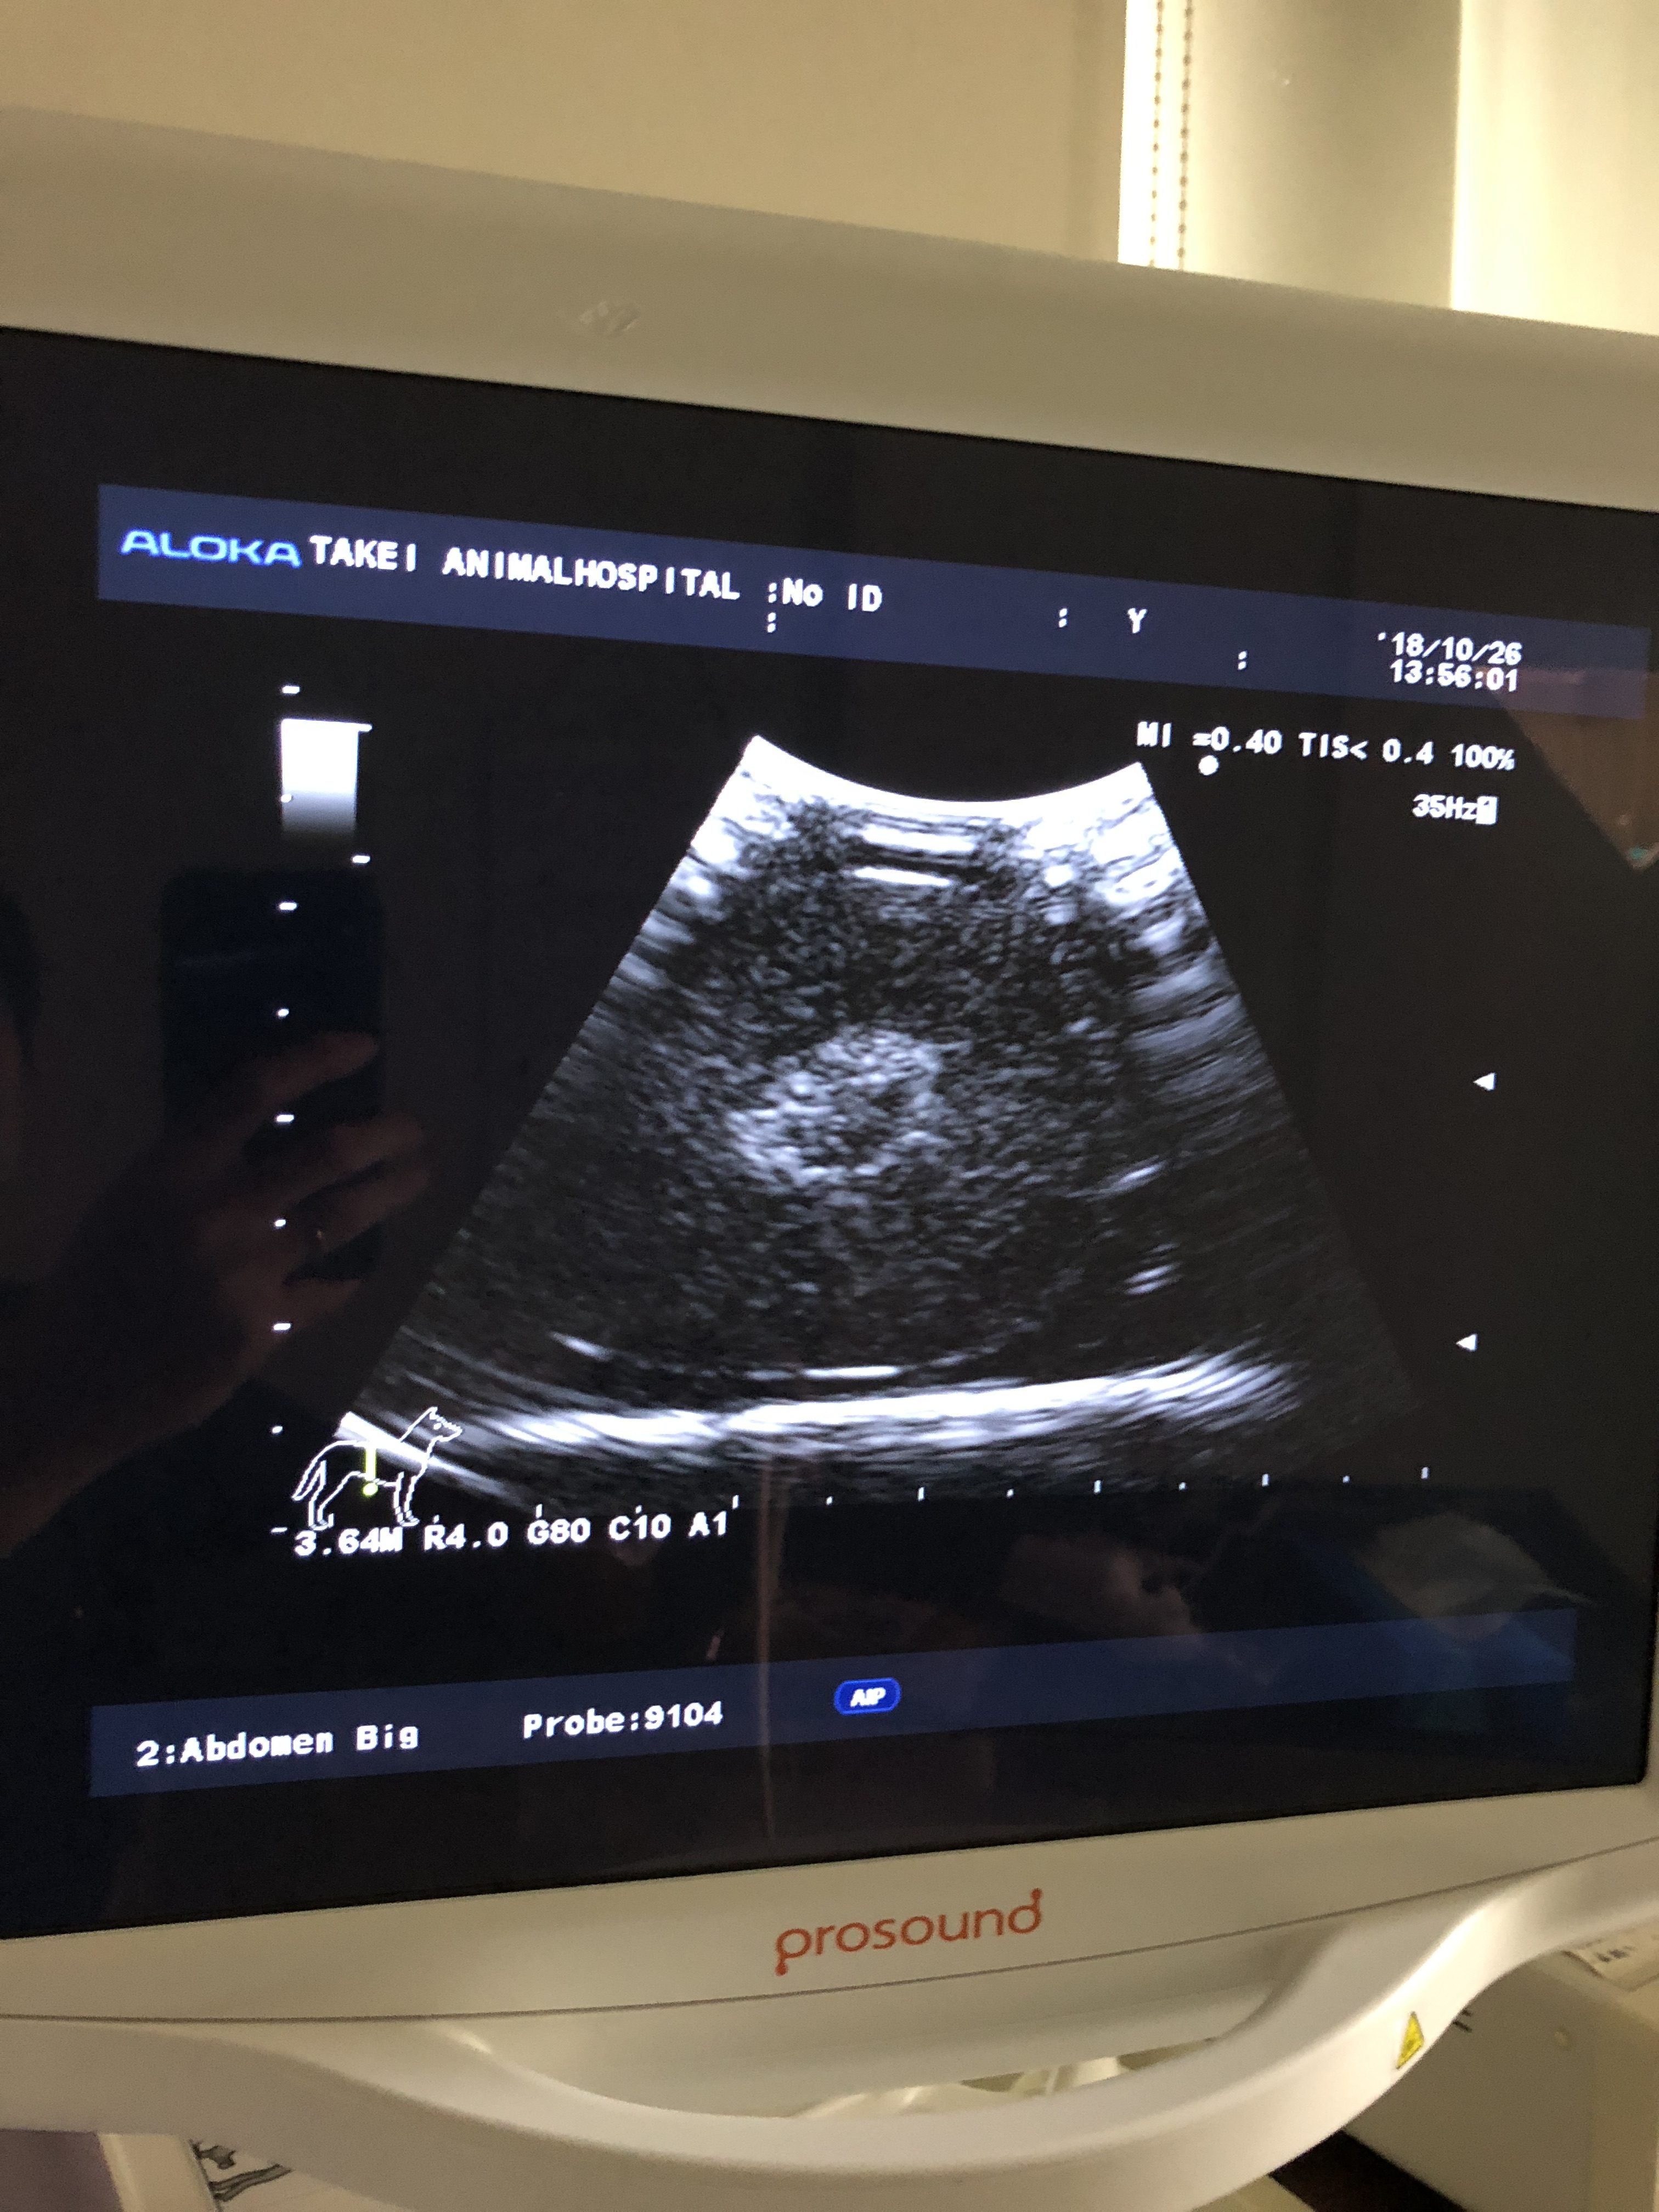

エコーで見ると以下のように見えます。

ちくわ